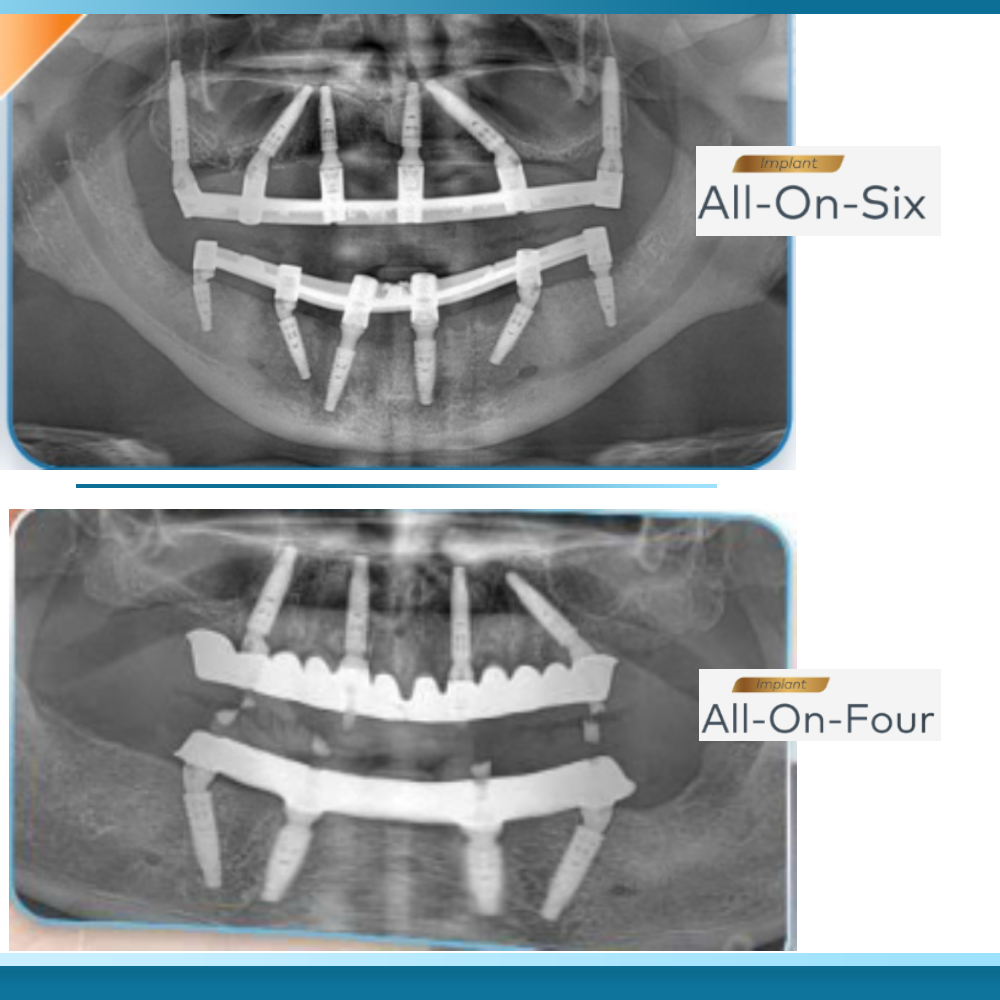

Sự khác biệt về kỹ thuật đặt trụ giữa All on 4 và All on 6

Kỹ thuật phục hình toàn hàm bằng phương pháp All on 4 và All on 6 đều được coi là những bước tiến vượt bậc trong nha khoa hiện đại, giúp khôi phục chức năng ăn nhai và thẩm mỹ cho những người mất răng toàn bộ. Tuy nhiên, sự khác biệt cốt lõi nằm ở số lượng và cách thức phân bổ các trụ Titanium trong xương hàm.

Phương pháp All on 4 thường sử dụng bốn trụ Implant, trong đó hai trụ phía trước được đặt thẳng đứng và hai trụ phía sau được đặt nghiêng một góc lên đến 45 độ. Việc đặt nghiêng này là một chiến thuật kỹ thuật có chủ đích nhằm tận dụng tối đa vùng xương ở phía trước cung hàm, nơi thường có mật độ xương tốt nhất và ít bị tiêu biến theo thời gian, đồng thời giúp tránh được các cấu trúc giải phẫu nhạy cảm như xoang hàm ở hàm trên và dây thần kinh răng dưới ở hàm dưới.

Ngược lại, Trồng răng Implant All on 6 đòi hỏi một cách tiếp cận khác biệt khi bổ sung thêm hai trụ Implant ở vùng răng hàm phía sau. Các trụ này thường được đặt thẳng đứng hoặc chỉ hơi nghiêng nhẹ để tạo ra một hệ thống nâng đỡ toàn diện hơn cho cầu răng sứ bên trên.

Trong khi All on 4 tập trung lực vào bốn điểm trọng yếu, All on 6 chia nhỏ lực nhai lên sáu điểm, nhưng điều này đồng nghĩa với việc bác sĩ cần tìm thấy sáu vị trí có đủ thể tích xương (cả về chiều cao và chiều rộng) để đảm bảo các trụ có thể đứng vững và không xâm phạm lẫn nhau.